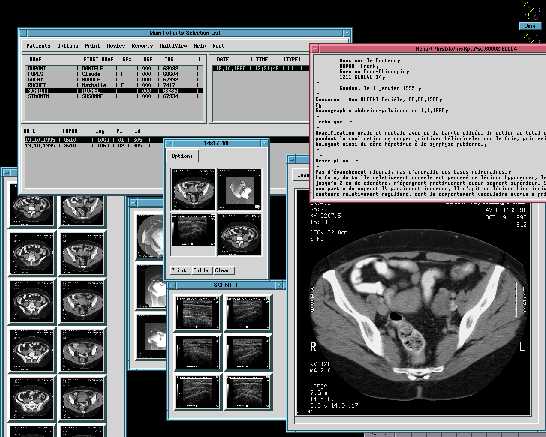

Esto es lo que dije a un amigo suizo que me llamo aqui en España, este explotaba Solaris, X11R4 y Motif 1.1 para los PC's, cada licencia le costaba la bagatela de 8.000 dolares y estaba buscando algo "mas barato", le comente el coste de Linux, no me colgo el telefono porque me tiene aprecio, pero si que me dijo algo que sonaba a "borracho", el caso es que lo compro. Este buen hombre posee una empressa (DAPSYS. SA ) dedicada a la informatica hospitalaria, su especilidad es el archivado de imagenes radiologicas y su restitucion en pantalla, sea con X11 y Motif o Win95.

Esta empresa tenia unas pocas instalaciones ya realizadas en Suiza, cuando de Canada se les presento un dia (casi sin avisar) dos vendedores de una muy importante empresa americana, estos no venian a vender sino comprobar "algo" que "alguien" les habia comentado en el RSNA de Chicago, el RSNA es el evento mundial en el tema de la radiologia. Dos meses despues el director de Dapsys se fue hacia Montreal con su "portatil" para enseñar el producto a unos cuantos doctores, tres meses despues (y 504 años despues de Colon) llego yo a las Americas para hacer la primera instalacion en aquel continente de Iris. Iris es la aplicacion de archivado y restitucion de imagenes radiologicas.

Ademas Iris permite centralizar por paciente TODOS los eventos radiologicos, cada imagen tiene grabada en ella el nombre, apellidos y codigo de paciente, Iris es capaz, mediante tratamiento OCR, extaer esos datos de la imagen y archivar la o las imagenes del paciente junto a las existentes (de haberlas).

Las estaciones de trabajo IRIS/Motif son para hacer una labor de, principalmente, de visualizacion con diagnostico, gracias que pueden pilotar hasta cuatro pantallas, de momento solo tienen 2 de 20 pulgadas, las busquedas en la base de datos se pueden resumir en :

• - Por datos del paciente

• - Fecha de examen, nacimiento

• - Modalidad

• - Patologia

• - Palabra clave

Las estaciones de trabajo IRIS/Win95 realizan la misma labor que las de Motif, con la salvedad que suelen ser instaladas en material ya existente y solo sirven como apoyo al diagnostico y no a su consecucion.